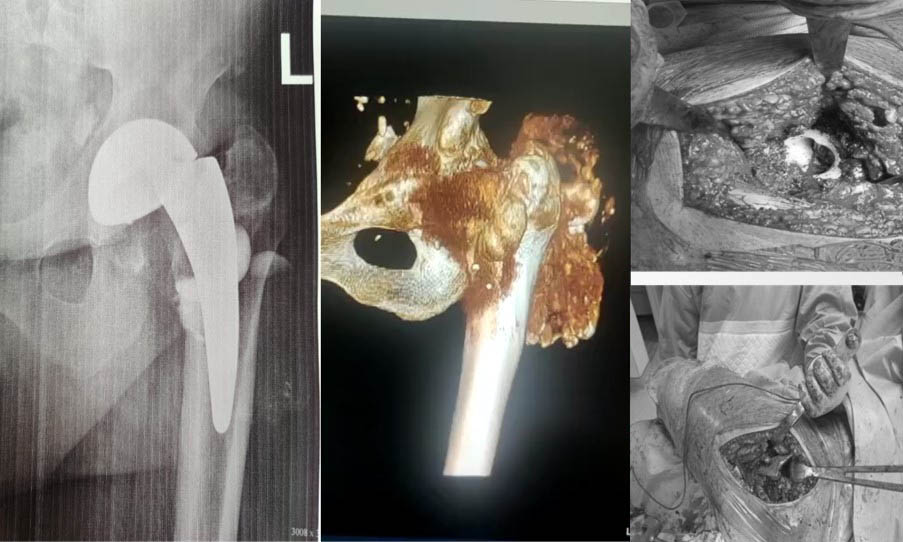

КЛІНІЧНИЙ ВИПАДОК. Пацієнт Г. 60 років. Оперований вісім років тому. Злам керамічної голівки, дефекти кісткової тканини та руйнування ендопротеза.

За допомогою лабораторії виконано ревізійне ендопротезування, сплановано хід та виконання ревізії, підготовлено необхідний інструментарій та надана допомога в виконанні операції.